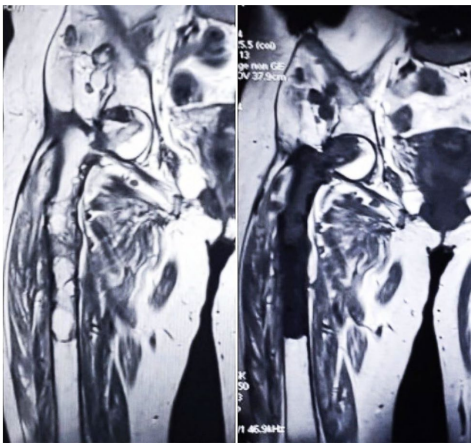

针对罕见但极具破坏性的骨包虫病(Osseous Hydatidosis),突尼斯研究团队提出创新性治疗方案:通过en bloc resection(整块切除)彻底清除病灶,结合mega prosthesis(巨型假体)重建肱骨与股骨功能。两例患者(肱骨全段感染、股骨近端广泛破坏)术后分别随访1.5年与5年,均实现无复发且肢体功能显著恢复(Constant肩评分65,Mayo肘评分70,LEFS下肢功能保留71.3%)。该研究为晚期骨包虫病的根治提供了类肿瘤外科治疗范式,显著降低48%的高复发风险。

骨包虫病——这种由细粒棘球绦虫(Echinococcus granulosus)引发的寄生虫感染,在骨骼系统中的发生率不足总病例的4%,却因其"沉默的侵袭"特性成为临床难题。寄生虫在骨髓腔内缓慢扩张,通过机械压迫、血管阻塞和骨质溶解三重机制蚕食骨骼,过程可长达数年而无明显症状。当患者因疼痛或病理性骨折就诊时,病灶往往已蔓延至整段长骨。传统刮除术因无法清除微小子囊,复发率高达48%,而抗寄生虫药物阿苯达唑(Albendazole)因骨组织穿透力差疗效有限。面对这种被喻为"白色癌症"的疾病,突尼斯的研究团队提出颠覆性思路:借鉴骨肿瘤根治理念,实施整块切除联合定制假体重建。

研究团队强调,尽管骨包虫发病率低,但MRI多房囊性征象(